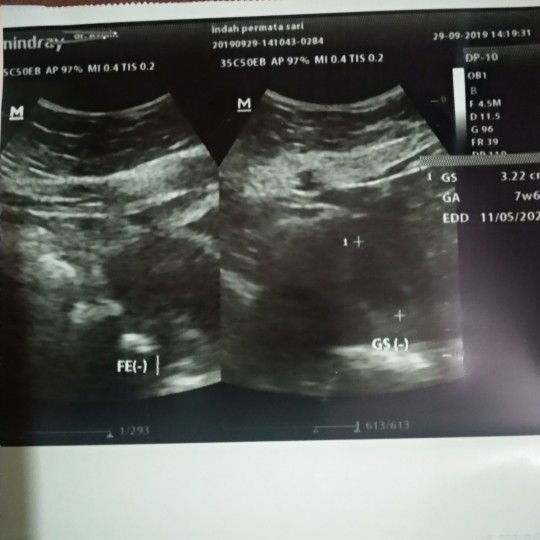

HASIL USG

Bun mau tanya kmren aku USG pertama di usia kehamilan 7week trus hpl (11/05/20) Nah..USG ke Dua di RS berbeda usia kehamilan 10week terus hpl (16/05/20) apa emng slalu berbeda atau gimna??

USG Kehamilan

Bun, kemarin kan saya usg di usia kehamilan 7week pas diusg hasilnya belum keliatan janinnya cuma baru kantungnya, kalo gitu normal ga ya Bun? Atau ada yg pernah ngalamin?